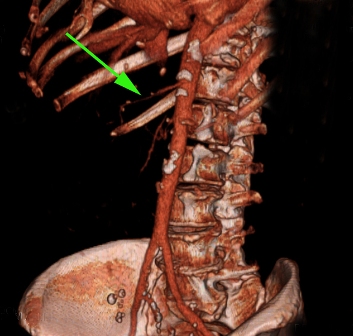

Компьютерная томография. 3D реконструкция. Показано место сужения верхней брызжеечной артерии.